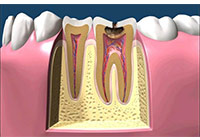

齲齒由口腔中多種因素復合作用所導致的牙齒硬組織進行性病損,表現為無機質脫礦和有機質分解,隨病程發展而從色澤改變到形成實質性病損的演變過程。齲齒是細菌性疾病,因此它可以繼發牙髓炎和根尖周炎,甚至能引起牙槽骨和頜骨炎癥。(圖01~04)

圖1

圖2